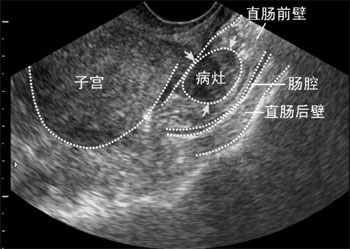

纳氏宫颈囊肿,即宫颈腺囊肿,也称为纳博特囊肿、宫颈纳氏囊肿、纳氏腺囊肿,简称为“纳囊”,同宫颈糜烂、宫颈息肉一样,是慢性宫颈炎的一种表现。

病理:在宫颈糜烂愈合过程中,新生的鳞状上皮覆盖宫颈腺管口或伸入腺管,将腺管口阻塞;或腺管周围的结缔组织增生或瘢痕形成压迫腺管,使腺管变窄甚至阻塞,腺体分泌物引流受阻,滞留形成的囊肿。

纳氏宫颈囊肿可发生于宫颈的任何部位,可单个出现,亦可多个出现。